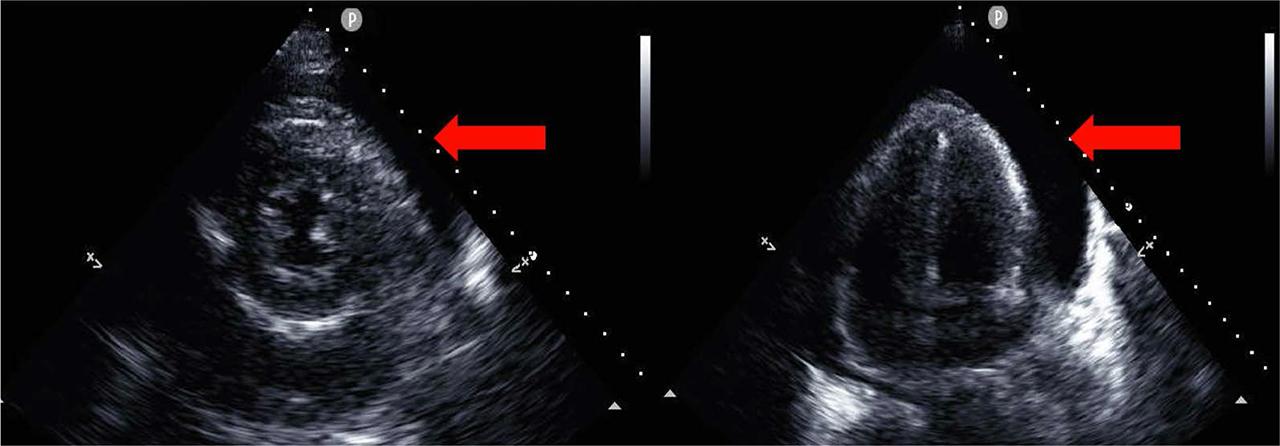

Initial room progress. The 12-lead electrocardiogram showed no obvious ST-segment elevation. Echocardiography showed circumferential pericardial effusion but no obvious aortic flap (Figure 1A,B). The left ventricular ejection fraction was approximately 60%, and there was no obvious regional wall motion abnormality. Contrast-enhanced computed tomography (CT) showed no evidence of cardiac wall thinning or aortic dissection, but a large amount of pericardial effusion was observed. A high CT value of 40 HU was observed, suggesting a hematogenous pericardial effusion. The patient also had bilateral pleural effusions. After returning to the room, he was diagnosed with obstructive shock due to cardiac tamponade because of a rapid decrease in blood pressure and progressive metabolic acidosis. After tracheal intubation and pericardiocentesis under ventilatory control, 800 ml of bloody pericardial fluid was removed, and the blood pressure increased thereafter. As differential diagnoses of cardiac tamponade caused by bloody pericardial fluid, we considered and ruled out acute aortic dissection and acute myocardial infarction based on various examination findings. Comparison of blood images of the pericardial fluid and peripheral blood showed a high ratio of blasts in the pericardial fluid, suggesting that the MDS had acutely metastasized in the pericardial space, leading to cancerous pericardial effusion and cancerous cardiac tamponade. A pericardial drain was placed, and the patient was admitted to the intensive care unit.

A,B, Echocardiography on arrival to the hospital. A, Parasternal left border left ventricular short-axis image showing pericardial effusion (red arrow). B, The apical tetralogy of the pericardium also shows pericardial effusion (red arrow).